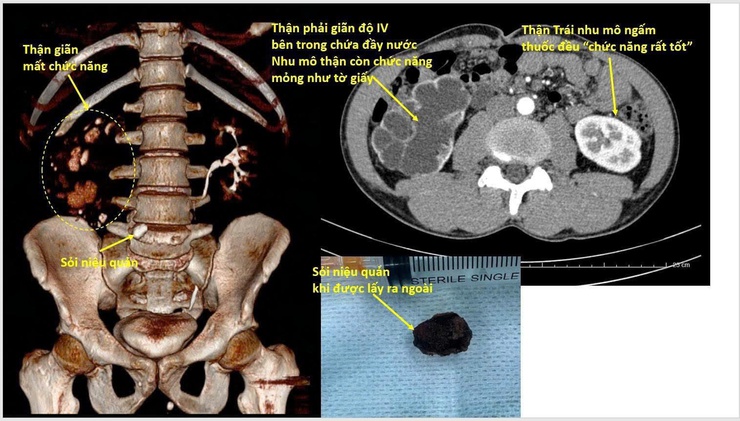

Qua thăm khám lâm sàng kết hợp với các xét nghiệm và chẩn đoán hình ảnh, các bác sĩ xác định bệnh nhân có sỏi niệu quản kích thước lớn khoảng 20mm, gây tắc nghẽn niệu quản kéo dài, thận giãn độ IV, nhu mô thận teo mỏng, gần như mất chức năng. Trước tình trạng này, bệnh nhân được chỉ định nhập viện ngay để điều trị.

Khai thác bệnh sử cho thấy, trước đó bệnh nhân từng được chẩn đoán có sỏi niệu quản kích thước lớn (~20mm). Tuy nhiên, khi kiểm tra tại một cơ sở gần nhà, kết quả siêu âm lại ghi nhận kích thước nhỏ hơn (khoảng 8mm).

Từ nhận định này khiến bệnh nhân chủ quan, không đến cơ sở chuyên khoa để theo dõi mà tự điều trị tại nhà, sử dụng thuốc theo tư vấn của người quen trong thời gian dài. Hệ quả là trong suốt quá trình tự điều trị viên sỏi không được xử lý triệt để, tình trạng tắc nghẽn niệu quản kéo dài, nước tiểu ứ đọng tại thận.

Khi đến khám Bệnh viện Thận Hà Nội, chức năng thận đã mất hoàn toàn, không còn khả năng bảo tồn.

Trước diễn tiến nghiêm trọng, các bác sĩ Khoa Ngoại Thận - Tiết niệu đã chỉ định phẫu thuật cắt bỏ thận mất chức năng nhằm tránh các biến chứng nguy hiểm. Sau phẫu thuật, bệnh nhân được theo dõi, chăm sóc theo đúng phác đồ. 1 tuần sau điều trị, tình trạng bệnh nhân ổn định và được xuất viện.